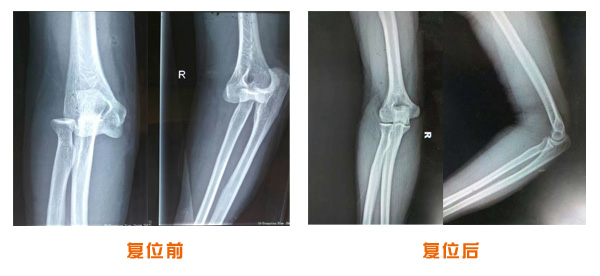

肘關節脫位骨折治療前后對比